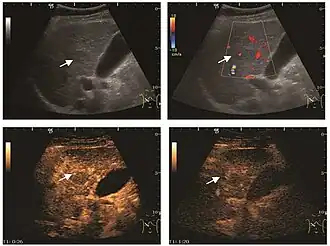

Hydatid liver cyst. Diagnostic criteria are the presence of membranes and sediment inside.